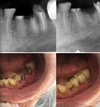

Diş Ağrısı

Diş Çürükleri

Diş ve Diş eti hastalıkları